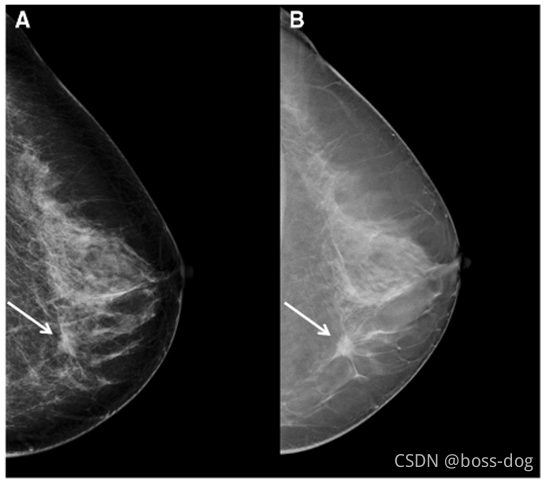

Mammography(乳腺癌钼靶成像)

分辨率很高。

A:数字化钼靶片(digital mammography),是透射图像,相当于整个乳腺的每一层的组织都把它重叠到一张图。

B:层析X射线照相组合(Tomosynthesis),通过不同的角度得到透视图,从而重建出断面的图像,看的更清楚,就可以去掉那些不同高度的图像组织的重叠。